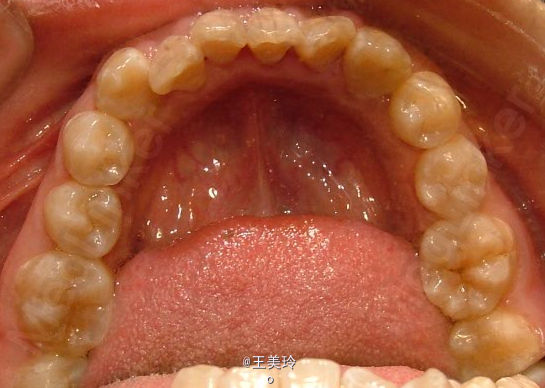

主诉:面突求矫治 既往史:无矫治史,无牙科治疗史,无外伤史,无过敏史,无口腔不良习惯,无家族遗传史 口腔检查:恒牙列,A7-B7;C7-D7。个别牙齿不齐 尖牙磨牙I类关系轻度深覆合深覆盖 下颌中线右偏约2mm 双颌前突,突面型 关节无弹响无压痛

诊断:安氏I类双颌前突 矫治计划 1.MBT矫治技术 2.拔牙矫治,拔A4B4C4D4 3.闭隙曲,J勾内收前牙 4.矫治结束后尖牙,磨牙,覆合覆盖正常 5.面型有所改善